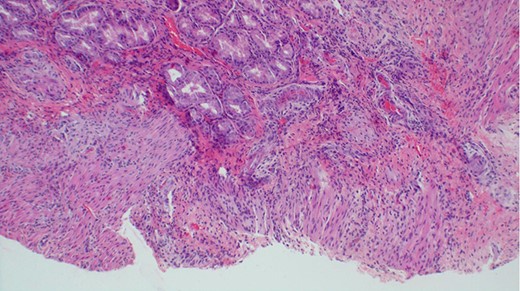

The baby was prepared and taken for an emergency laparotomy whereby intraoperatively, a gastric perforation was found measuring 0.5 by 0.5 cm, circumferential and located on the anterior aspect of the stomach body near the pylorus (Fig. 2). There was also about 50 ml of amber-colored ascites. The perforation was repaired and Grahm’s patch was put, thorough abdominal lavage and the abdomen was closed in layers. Biopsy from the perforation site revealed non-necrotizing mild chronic gastritis, not otherwise specified with ulcerations (Figs 3 and 4).

Histopathology of the biopsy from the gastric perforation showing near full thickness with non-specific mixed chronic inflammation (H&E staining, x10).

Histological appearance of gastric wall showing ulceration, mild chronic inflammation, focal hemorrhage and serosal fibrosis (H&E staining, ×20).